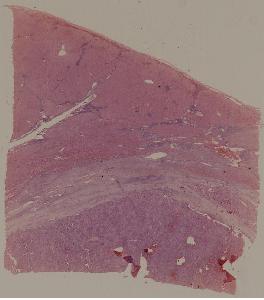

69.肝细胞性肝癌

低倍视野